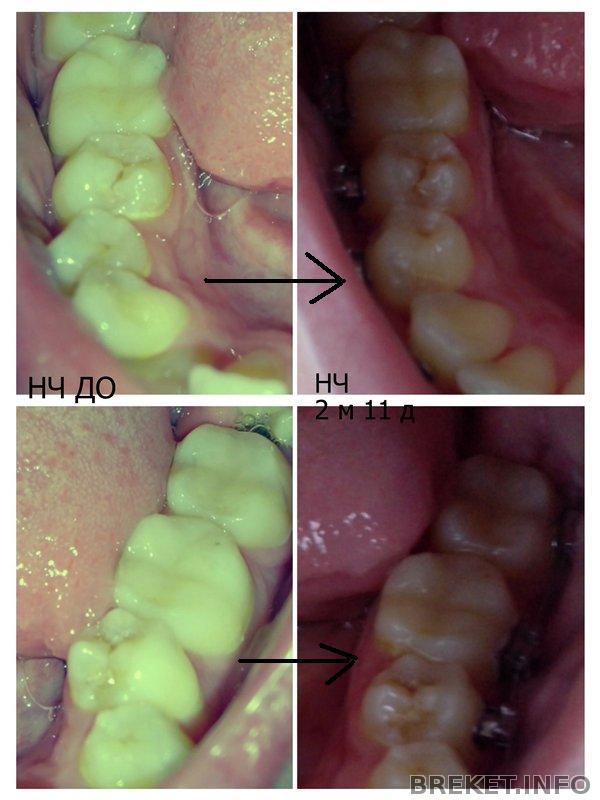

ВЧ И НЧ КОЛЛАЖ ИЗМЕНЕНИЙ

Таких ракурсов я еще не постила

Для удобства восприятия сделала стрелочки переходные))

Особенно зацените ВЧ: как выровнялись единички! Они были унылые опущенные, а теперь стали гордыми и поднятыми о_О